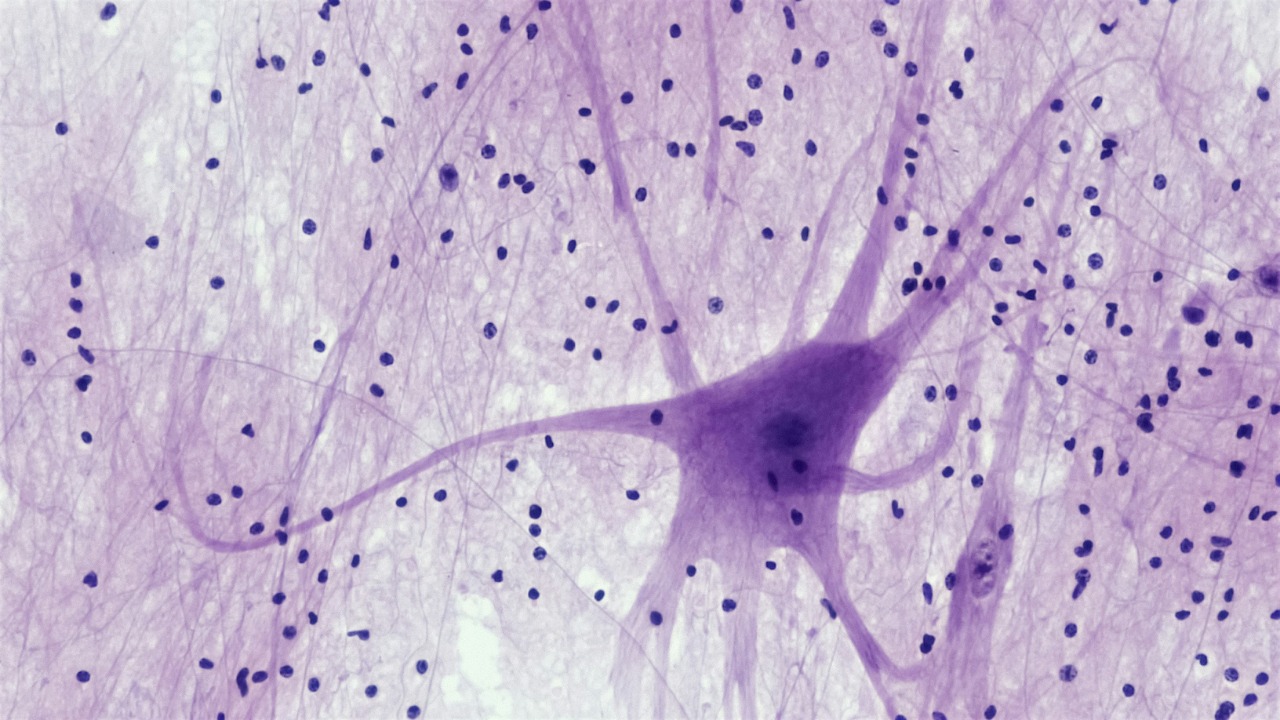

Neurogenesis, or the process of creating new neurons, is an ongoing biological process in the human brain. It was once believed that humans were born with a set number of neurons, and no new ones could be created after birth. However, recent studies have debunked this belief, illustrating that new neurons can indeed be formed in the adult brain.

Interestingly, silence appears to play a key role in this process. A quiet environment allows our brains to relax and focus, thereby encouraging neurogenesis. Research has shown that two hours of silence per day can significantly increase the production of new neurons, offering a simple and accessible method for boosting brain health.